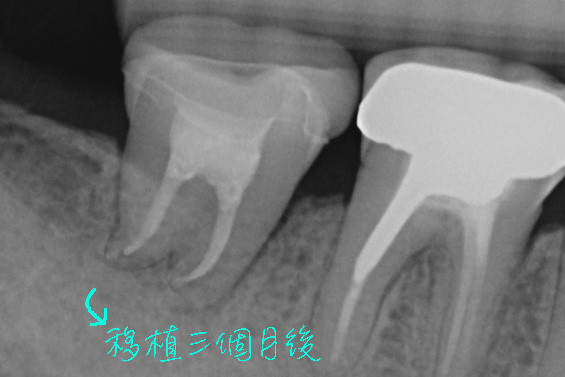

本案例的臼齒因為斷裂而必須拔除,我們把後方的智齒往前搬家,直接取代壞掉的牙齒,等到傷口癒合好後又可以正常咀嚼食物了。